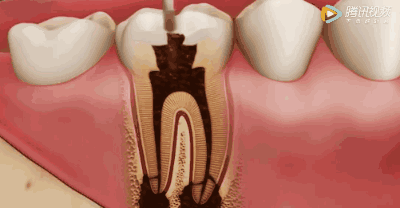

钻开腐败的牙质

去净腐质和原有充填物,看到整个髓底解剖结构以便后续治疗顺利进行。